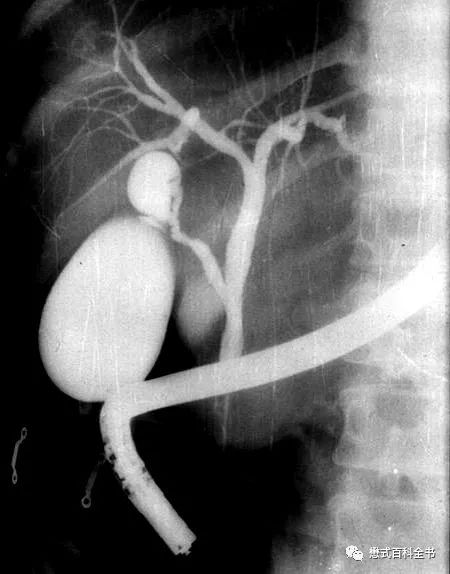

图1:ERCP示意图

和MRCP类似的一个单词叫做ERCP(Endoscopic Retrograde CholangioPancreatography),翻译过来就是(经内镜)逆行性胰胆管造影术。Endo-是内、在内的前缀,-scopic表示观测、观察,当然endoscopic这个词本来就是内窥镜的,用内镜的方式的意思。Retro-是一个使用比较多的前缀,代表向后的,回顾的,*退倒**的。大家还记得我们的回顾性心电门控是怎么表述的吗?Retrospective,回顾性研究,回顾性分析都是这个前缀。grade这个单词大家熟悉,可以理解为年级、级别、阶段。

retrograde就很好理解了,为了信达雅和结合技术把它翻译为逆行性的。而同样的单词cholangiopancreatography在MRCP中翻译为成像,在ERCP中翻译为造影术更恰当。因为ERCP是一种有创性的手术方式,并且会注入造影剂以使胆囊及胆管系统显影,所以用造影术是比较合适的。